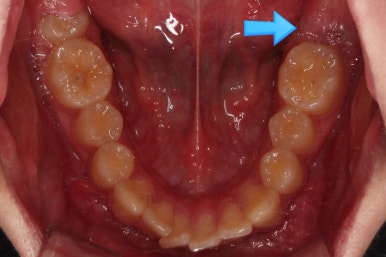

대신, 우측 아래 화살표를 보시면 나와야 될 어금니가 나오지 못하고 있는 상황이었어요.

X-ray를 보면 사랑니가 어부바 하고 있어서 나와야 될 어금니가 짓눌려 있는 양상이었어요.

이 경우 방향을 잘못잡아서 바로 앞 어금니도 밀어버리거나 해를 가할 수 있는 상황이었어요.

사랑니가 잘못나는 바람에 사랑니 포함 치아 3개가 문제가 될 수 있는 상황이었어요.